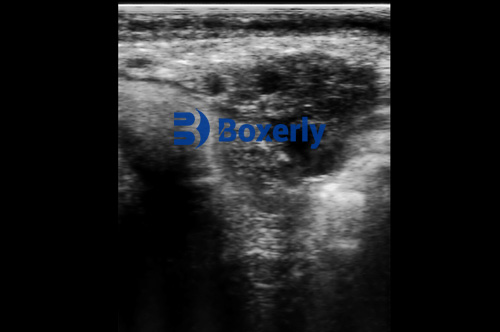

Bovine ultrasound allows veterinarians to view the cow’s ovaries in real time. Unlike palpation, ultrasound shows the size, shape, and structure of the ovarian tissue and any cysts present. Farmers can determine whether a cyst is functional (potentially resolving on its own) or pathological (requiring intervention).

With ultrasound, multiple cysts or unusual structures are easily identified. Early diagnosis helps plan treatment and prevent unnecessary insemination attempts. This reduces wasted semen, lowers breeding costs, and keeps the herd on schedule for predictable calving intervals.